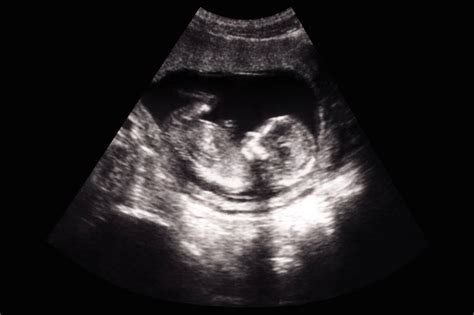

La espera de un nuevo miembro en la familia es una de las etapas más emocionantes y transformadoras en la vida de una persona. Durante este periodo, una de las herramientas más valiosas para el seguimiento médico y la conexión emocional entre los padres y el bebé son las ecografías de embarazo. Estos estudios por imágenes no solo permiten al obstetra verificar el desarrollo correcto del feto, sino que también ofrecen a los futuros padres la oportunidad inolvidable de ver los primeros movimientos, escuchar los latidos del corazón y confirmar el bienestar general del pequeño. Entender qué esperar en cada etapa es fundamental para vivir este proceso con tranquilidad y mayor conocimiento.

Las ecografías de embarazo son procedimientos diagnósticos no invasivos que utilizan ondas sonoras de alta frecuencia para crear imágenes del feto, la placenta y el líquido amniótico dentro del útero. A diferencia de los rayos X, este método es totalmente seguro tanto para la madre como para el bebé, ya que no utiliza radiación ionizante. La importancia de realizarse estos estudios radica en la capacidad de detectar precozmente cualquier anomalía estructural, monitorear el crecimiento fetal y asegurar que el desarrollo se encuentre dentro de los parámetros normales de cada trimestre.

Además del aspecto médico, estas sesiones proporcionan una tranquilidad invaluable. Poder visualizar la anatomía del bebé ayuda a establecer un vínculo afectivo temprano, lo que puede reducir significativamente la ansiedad materna. Es una experiencia única que permite convertir la teoría del embarazo en una realidad tangible ante nuestros ojos.